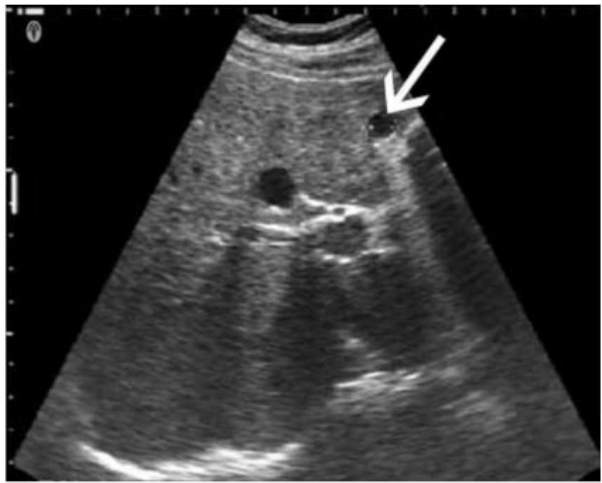

Which technique is best for demonstrating the characteristic of the small hepatic lesion identified by the arrow on this image?

The image shows a small hepatic lesion located very close to the anterior liver capsule, as indicated by the arrow. When imaging very superficial or near-field structures like subcapsular hepatic lesions, using a standoff pad is the most effective technique for optimizing visualization.

A standoff pad (also known as an acoustic stand-off or gel pad) helps increase the distance between the transducer and the superficial target. This improves the focus and beam shape for near-field imaging and minimizes reverberation and ring-down artifacts. It allows better evaluation of superficial lesions by positioning them within the focal zone of the transducer, which is usually set a few millimeters below the probe surface.